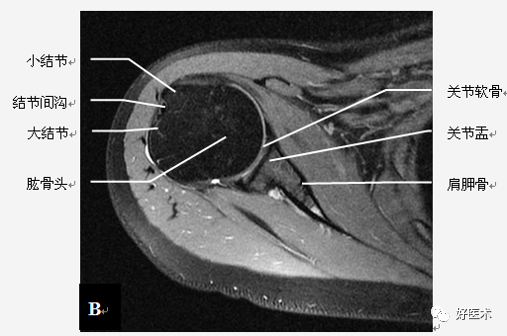

肩关节骨骼构成

三块骨:肩胛骨、锁骨、肱骨

两个关节:

肩锁关节

盂肱关节